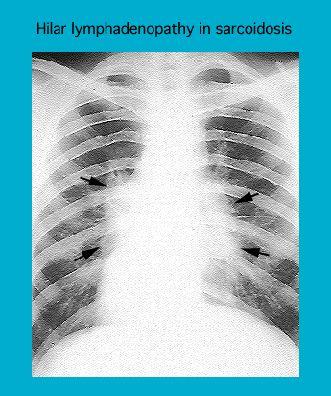

Radiographie montrant une lymphadénopathie hilaire dans le cas d'un sarcoïde